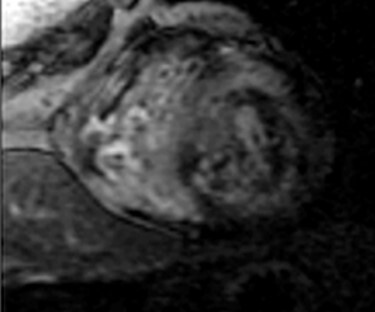

Figure 4 .

CMR showing concentric left ventricular hypertrophy.